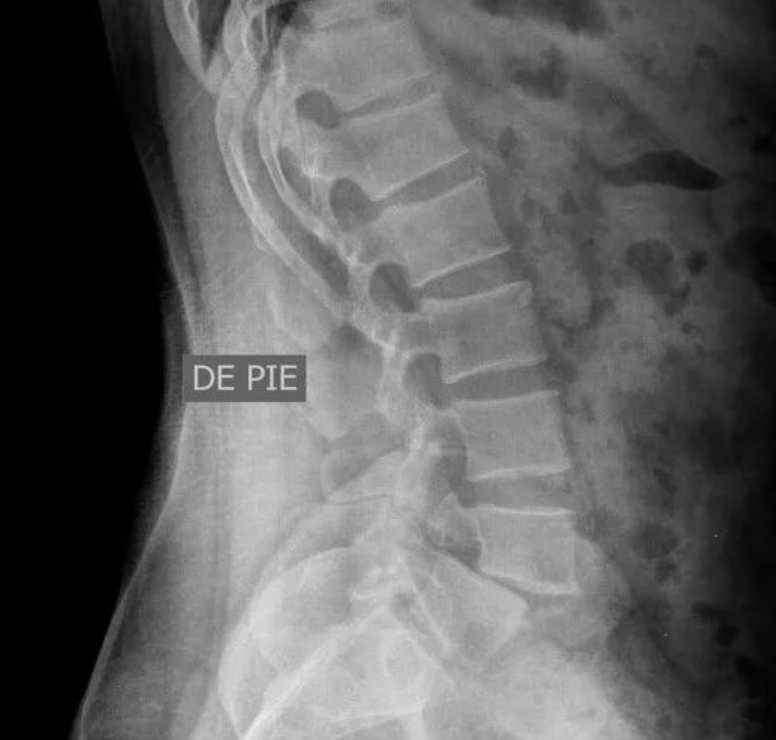

侧位片:椎弓根后下方细长或见透明裂隙,关节突间常见硬化征象;上位病变椎体出现滑移;椎间隙狭窄,椎间隙前后比例异常;可对滑脱程度进行具体测量。

图示:椎弓崩裂伴脊柱滑脱(侧位),第四腰椎椎弓崩裂,伴第四腰椎椎体向前滑脱,箭头示棘突后缘曲线异常。